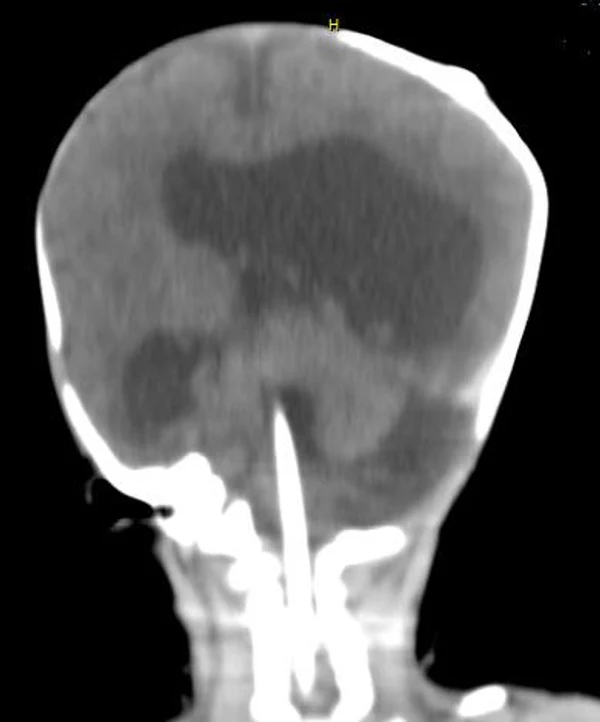

кисты, аномалии Денди-Уокера и др.Операции при внутричерепных кистах. В основном встречаются арахноидальные кисты различных локализаций и кисты сосудистых сплетений боковых желудочков. Пациентам с врождёнными кистами операции проводятся в следующих ситуациях: увеличении объема кисты в динамике, наличии клинических проявлений, компрессии и дислокации мозговых структур, наличии окклюзии ликворных путей. Нами используются 2 способа хирургического лечения кист: эндоскопическая перфорация стенок кист и открытая резекция кист. Открытая резекция кист проводится при ретроцеребеллярных арахноидальных кистах (рис. 2), при арахноидальных кистах межполушарной щели при отсутствии непосредственного контакта их стенок со стенками расширенных желудочков головного мозга и повторного увеличения кист средней черепной ямки после эндоскопической кисто-цистерностомии. Техника операции заключается в проведение краниотомии и максимальном иссечении стенок кист с созданием широкого сообщения кист с субарахноидальным пространством. Эндоскопические операции проводятся при арахноидальных кистах межножковой и пинеальной цистерн, арахноидальных кистах межполушарной щели при тесном контакте их стенок со стенками расширенной желудочковой системы (рис. 3), первично при арахноидальных кистах средней черепной ямки, а также при кистах сосудистых сплетений боковых желудочков. При арахноидальных кистах межножковой цистерны эндоскопически проводится перфорация стенок кисты, сообщая ее с просветом III желудочка и межножковой цистерной – эндоскопическая вентрикуло-кисто-цистерностомия (рис. 4). При арахноидальных кистах пинеальной цистерны проводится перфорация кисты в передне-верхних её отделах с созданием сообщения полости кисты с просветом III желудочка – эндоскопическая кисто-вентрикулостомия. С целью предотвращения облитерации сформированного отверстия иногда в полость кисты под контролем эндоскопа вводится стент перфорированный на протяжении (рис. 5, 6). Эндоскопическая кисто-цистерностомия выполняется при арахноидальных кистах средней черепной ямки. При этом создается широкое сообщение кисты с базальными цистернами. При кистах сосудистых сплетений боковых желудочков проводится их вскрытие в просвет боковых желудочков – эндоскопическая кисто-вентрикулостомия. При множественных кистах проводится их хирургическое сообщение между собой – интеркистосмия